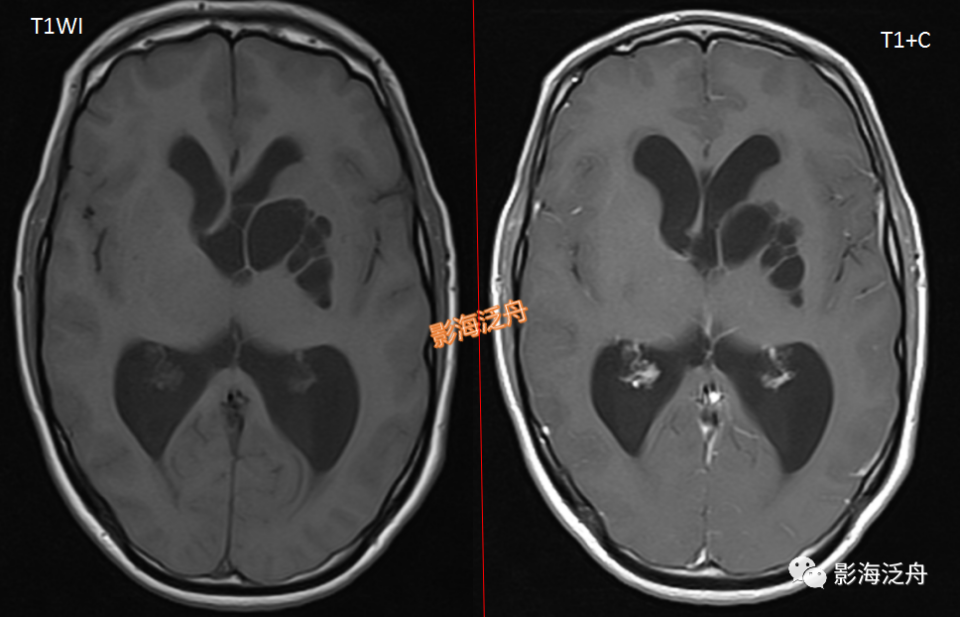

病例二:21岁女性患者,头痛数月前来就诊。左侧基底节区多发囊性病灶,部分突入第三脑室室间孔区域并引起梗阻性脑积水(红箭),病灶簇状分布,呈规则的圆形或类圆形,灶周无明显水肿,增强未见任何强化,符合扩大V-R腔隙的典型特征。值得注意的是,扩大的VR腔隙一般不会引起占位性效应。